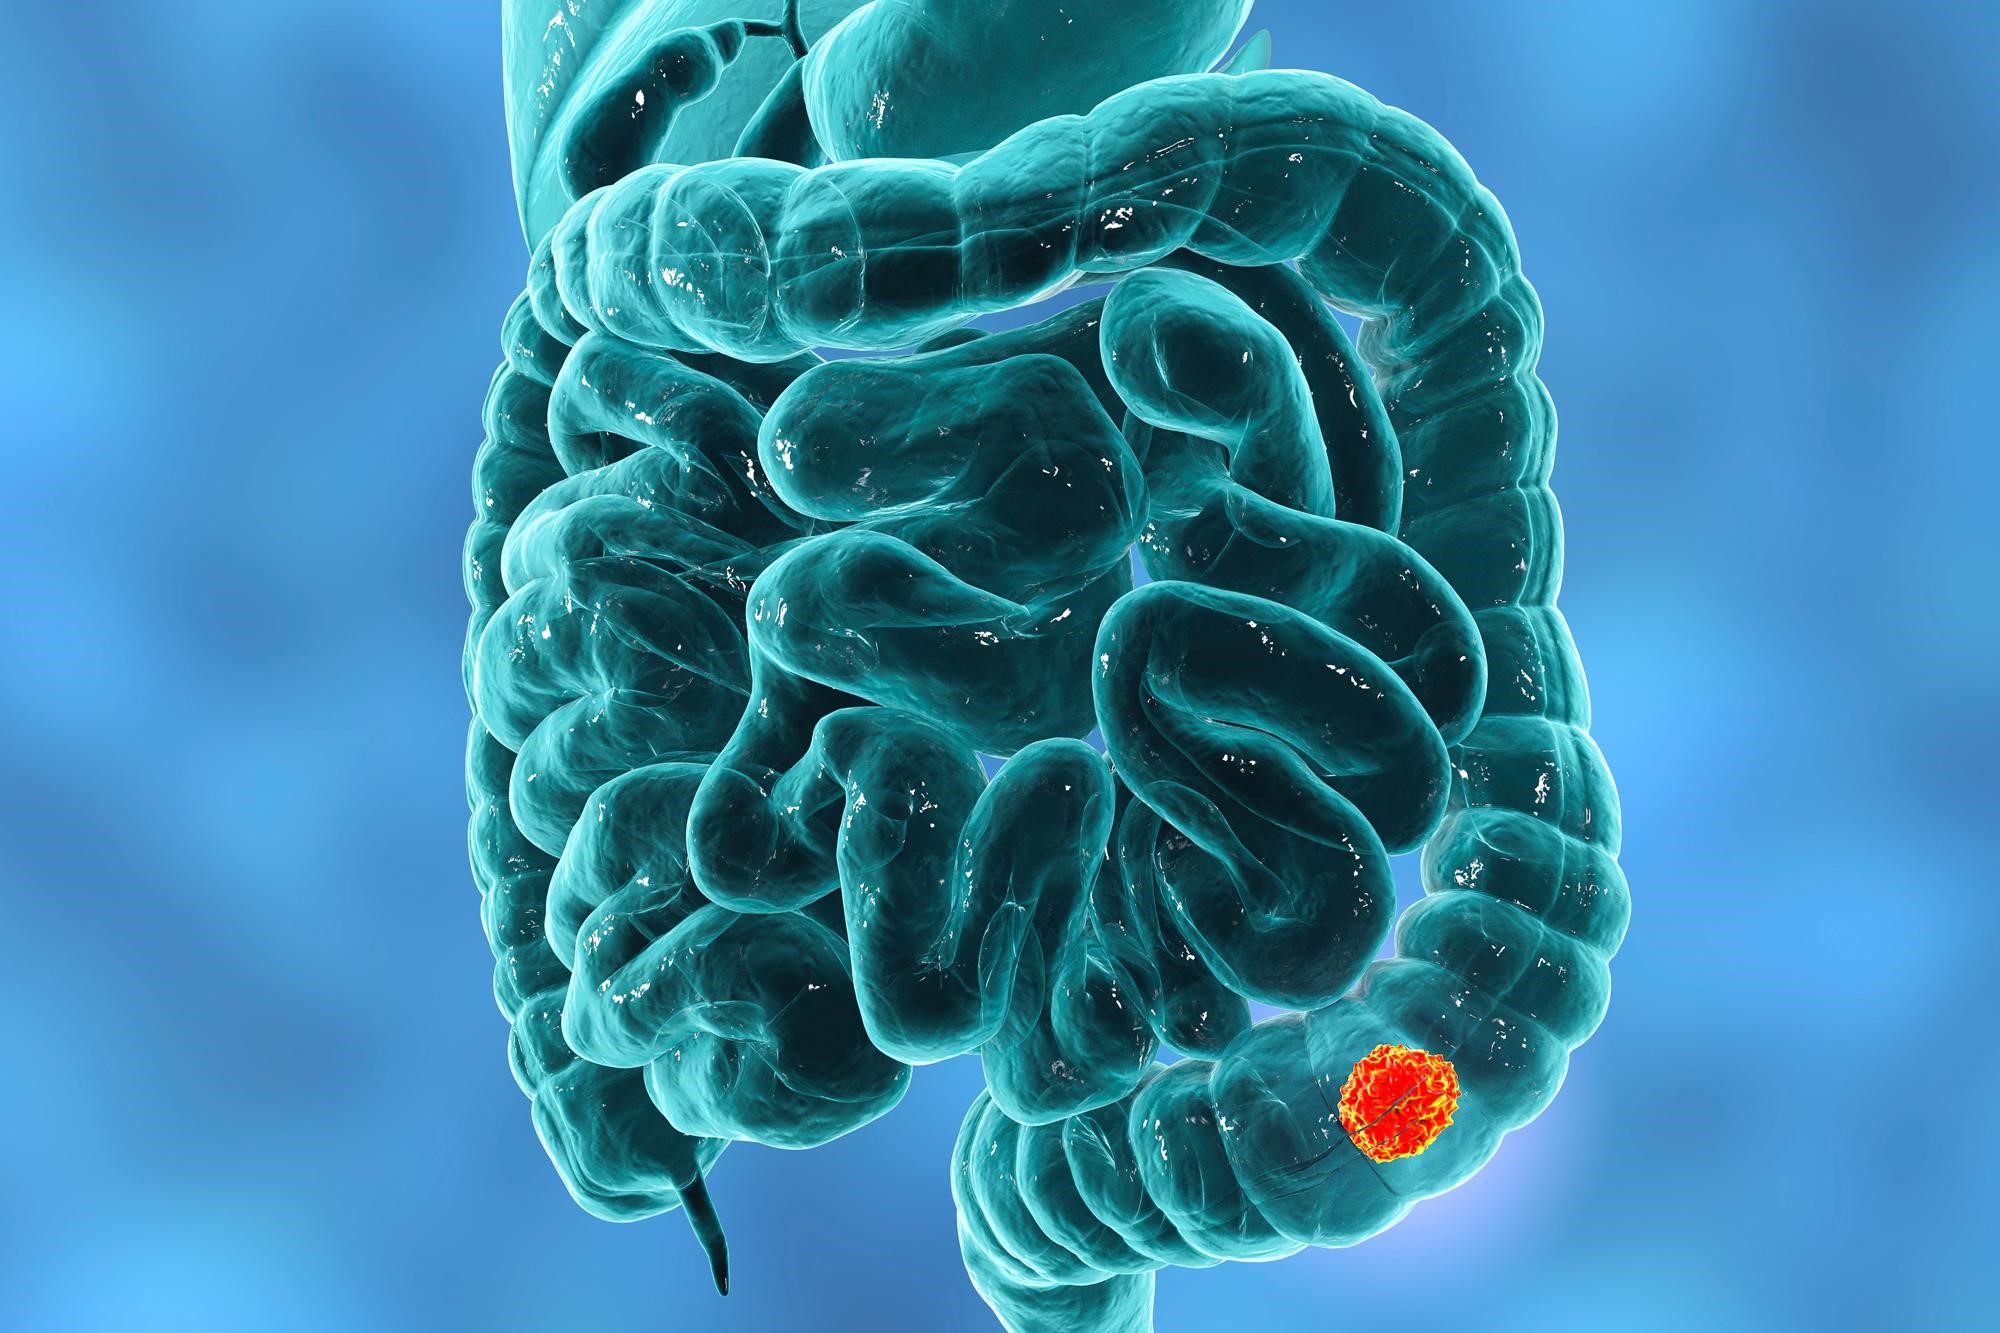

Ερευνητές ανακάλυψαν μια δραματική αύξηση στα περιστατικά καρκίνου του παχέος εντέρου, ιδιαίτερα μεταξύ παιδιών και εφήβων στις ΗΠΑ.

Από το 1999 έως το 2020, τα ποσοστά καρκίνου του παχέος εντέρου αυξήθηκαν κατά 500% σε παιδιά ηλικίας 10-14 ετών, κατά 333% σε έφηβους 15-19 ετών και κατά 185% σε νέους ενήλικες 20-24 ετών.

Χρησιμοποιώντας δεδομένα από τη βάση «Wonder Database» των Κέντρων Ελέγχου Ασθενειών των ΗΠΑ, οι ερευνητές κατέγραψαν τις τάσεις στα ποσοστά καρκίνου του παχέος εντέρου για άτομα ηλικίας 10-44 ετών από το 1999 έως το 2020.

Το 2020, 0,6 παιδιά ηλικίας 10-14 ετών ανά 100.000 πληθυσμού διαγνώστηκαν με καρκίνο του παχέος εντέρου, σε σύγκριση με 0,1 ανά 100.000 το 1999. Οι διαγνώσεις στους έφηβους 15-19 ετών αυξήθηκαν από 0,3 σε 1,3 ανά 100.000 και στους νέους ενήλικες 20-24 ετών από 0,7 σε 2 ανά 100.000.

Οι ερευνητές τονίζουν ότι, παρόλο που ο αριθμός των κρουσμάτων στα παιδιά και τους έφηβους δεν είναι αρκετά υψηλός για να δικαιολογήσει την ευρεία χρήση κολονοσκόπησης, θα πρέπει να εξεταστούν πιο εξατομικευμένες προσεγγίσεις.

Επιπλέον, διαπιστώθηκε αύξηση και σε μεγαλύτερες ηλικίες, με τα ποσοστά να αυξάνονται κατά 71% στις ηλικίες 30-34 ετών, κατά 58% στις ηλικίες 35-39 ετών και κατά 37% στις ηλικίες 40-44 ετών.

Η ηλικιακή ομάδα 40-44 ετών είχε τη μικρότερη ποσοστιαία αύξηση, αλλά το υψηλότερο ποσοστό εμφάνισης καρκίνου του παχέος εντέρου, φθάνοντας τα 20 περιστατικά ανά 100.000 άτομα το 2020.

Οι παράγοντες κινδύνου περιλαμβάνουν οικογενειακό ιστορικό φλεγμονώδους νόσου του εντέρου ή καρκίνου του παχέος εντέρου, ενώ οι τροποποιήσιμοι παράγοντες κινδύνου περιλαμβάνουν την παχυσαρκία, τη χρήση καπνού, και την κατανάλωση αλκοόλ.

Επίσης, διατροφικές συνήθειες όπως η χαμηλή πρόσληψη φυτικών ινών, η κατανάλωση επεξεργασμένων κρεάτων και ζαχαρούχων ποτών, και μια διατροφή πλούσια σε λιπαρά, είναι επίσης παράγοντες κινδύνου.

Πιθανοί, αλλά όχι σταθερά αποδεδειγμένοι παράγοντες, περιλαμβάνουν την καθιστική ζωή, την παρουσία βακτηρίων που τείνουν να προκαλούν όγκους, τη χρήση αντιβιοτικών και τα διατροφικά πρόσθετα.